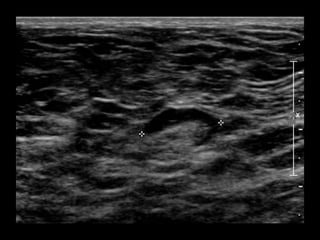

US retroareolar region

US Left upper outer breast

• What are the findings?

• What would you do next?

• What is your differential diagnosis?

• What are your recommendations?